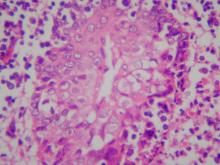

壞死灶。三、 組織病變: 肥前肉豬: 1.

腦:非化膿性腦膜腦炎,可見明顯之單核細胞圍管現象、神經膠質細胞過多及脫髓鞘

等病變(圖2)。2.

扁桃腺:瀰漫性壞死灶。 3.

淋巴結:可見凝固性壞死灶,壞死灶以細胞核之濃縮、破裂為主徵。 4.

肺臟:可見凝固性壞死灶及含纖維素性水腫液滲出,並可見化膿性支氣管性肺炎。 5.

肝臟:局部壞死灶,壞死區以細胞急性變性及細胞碎片兩種同時存在,並可見竇狀隙內有中性球及單核細胞浸潤。 6.

腎上腺:局部壞死灶,可見嗜酸性核內包涵體。 初生仔豬: 1.